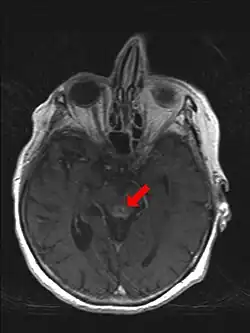

Zu Grunde liegt ein Vitamin-B1-Mangel (Thiamin), der zu Störungen im Kohlenhydratstoffwechsel durch Versagen einer energiereichen Phosphorylierung führt. Nach einer ödematösen Schwellung des Gehirns kommt es später auch zur Einblutung und Kapillarsprossung an bestimmten Stellen des Gehirns (Corpora mamillaria, hypothalamische Kerngebiete um den III. Ventrikel, Lamina tecti und periaquäduktales Grau mit Okulomotoriuskerngebieten). Es folgt eine Atrophie dieser Strukturen.